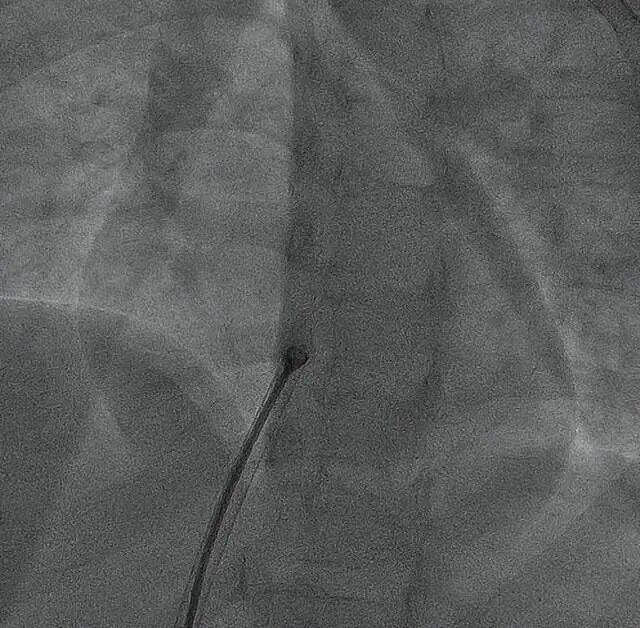

针对低龄患儿血管纤细、心脏结构未发育完全的特点,手术团队采用以超声引导为主、极少射线辅助的精准操作模式。术中超声全程实时清晰呈现心脏缺损位置、封堵器释放与贴合状态,在有效避免传统X射线对患儿辐射影响的同时,实现了40分钟内封堵器精准植入,且术后无残余分流。

▲封堵器释放,置入区域无任何异物显影